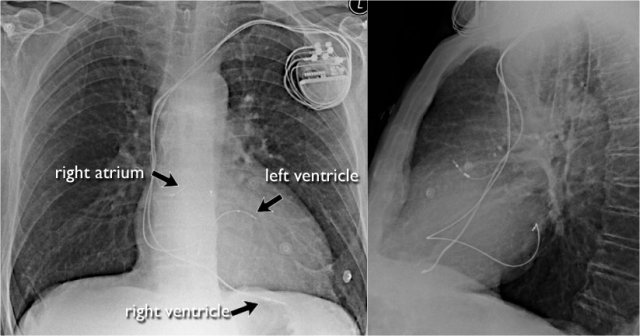

Pacemaker

There are different types of cardiac pacemakers.

Here we see a pacemaker with one lead in the right atrium and another in the right ventricle.

A third lead is seen, which is guided through the coronary sinus towards the left ventricle.

This is done in patients with asynchrone ventricular contractions.

Pacing both ventricles at the same time will lead to synchrone contractions and a better cardiac output.